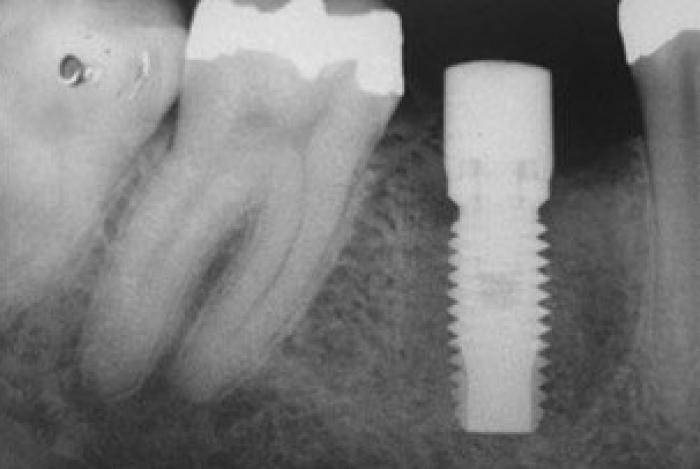

Raio X após a instalação do implante